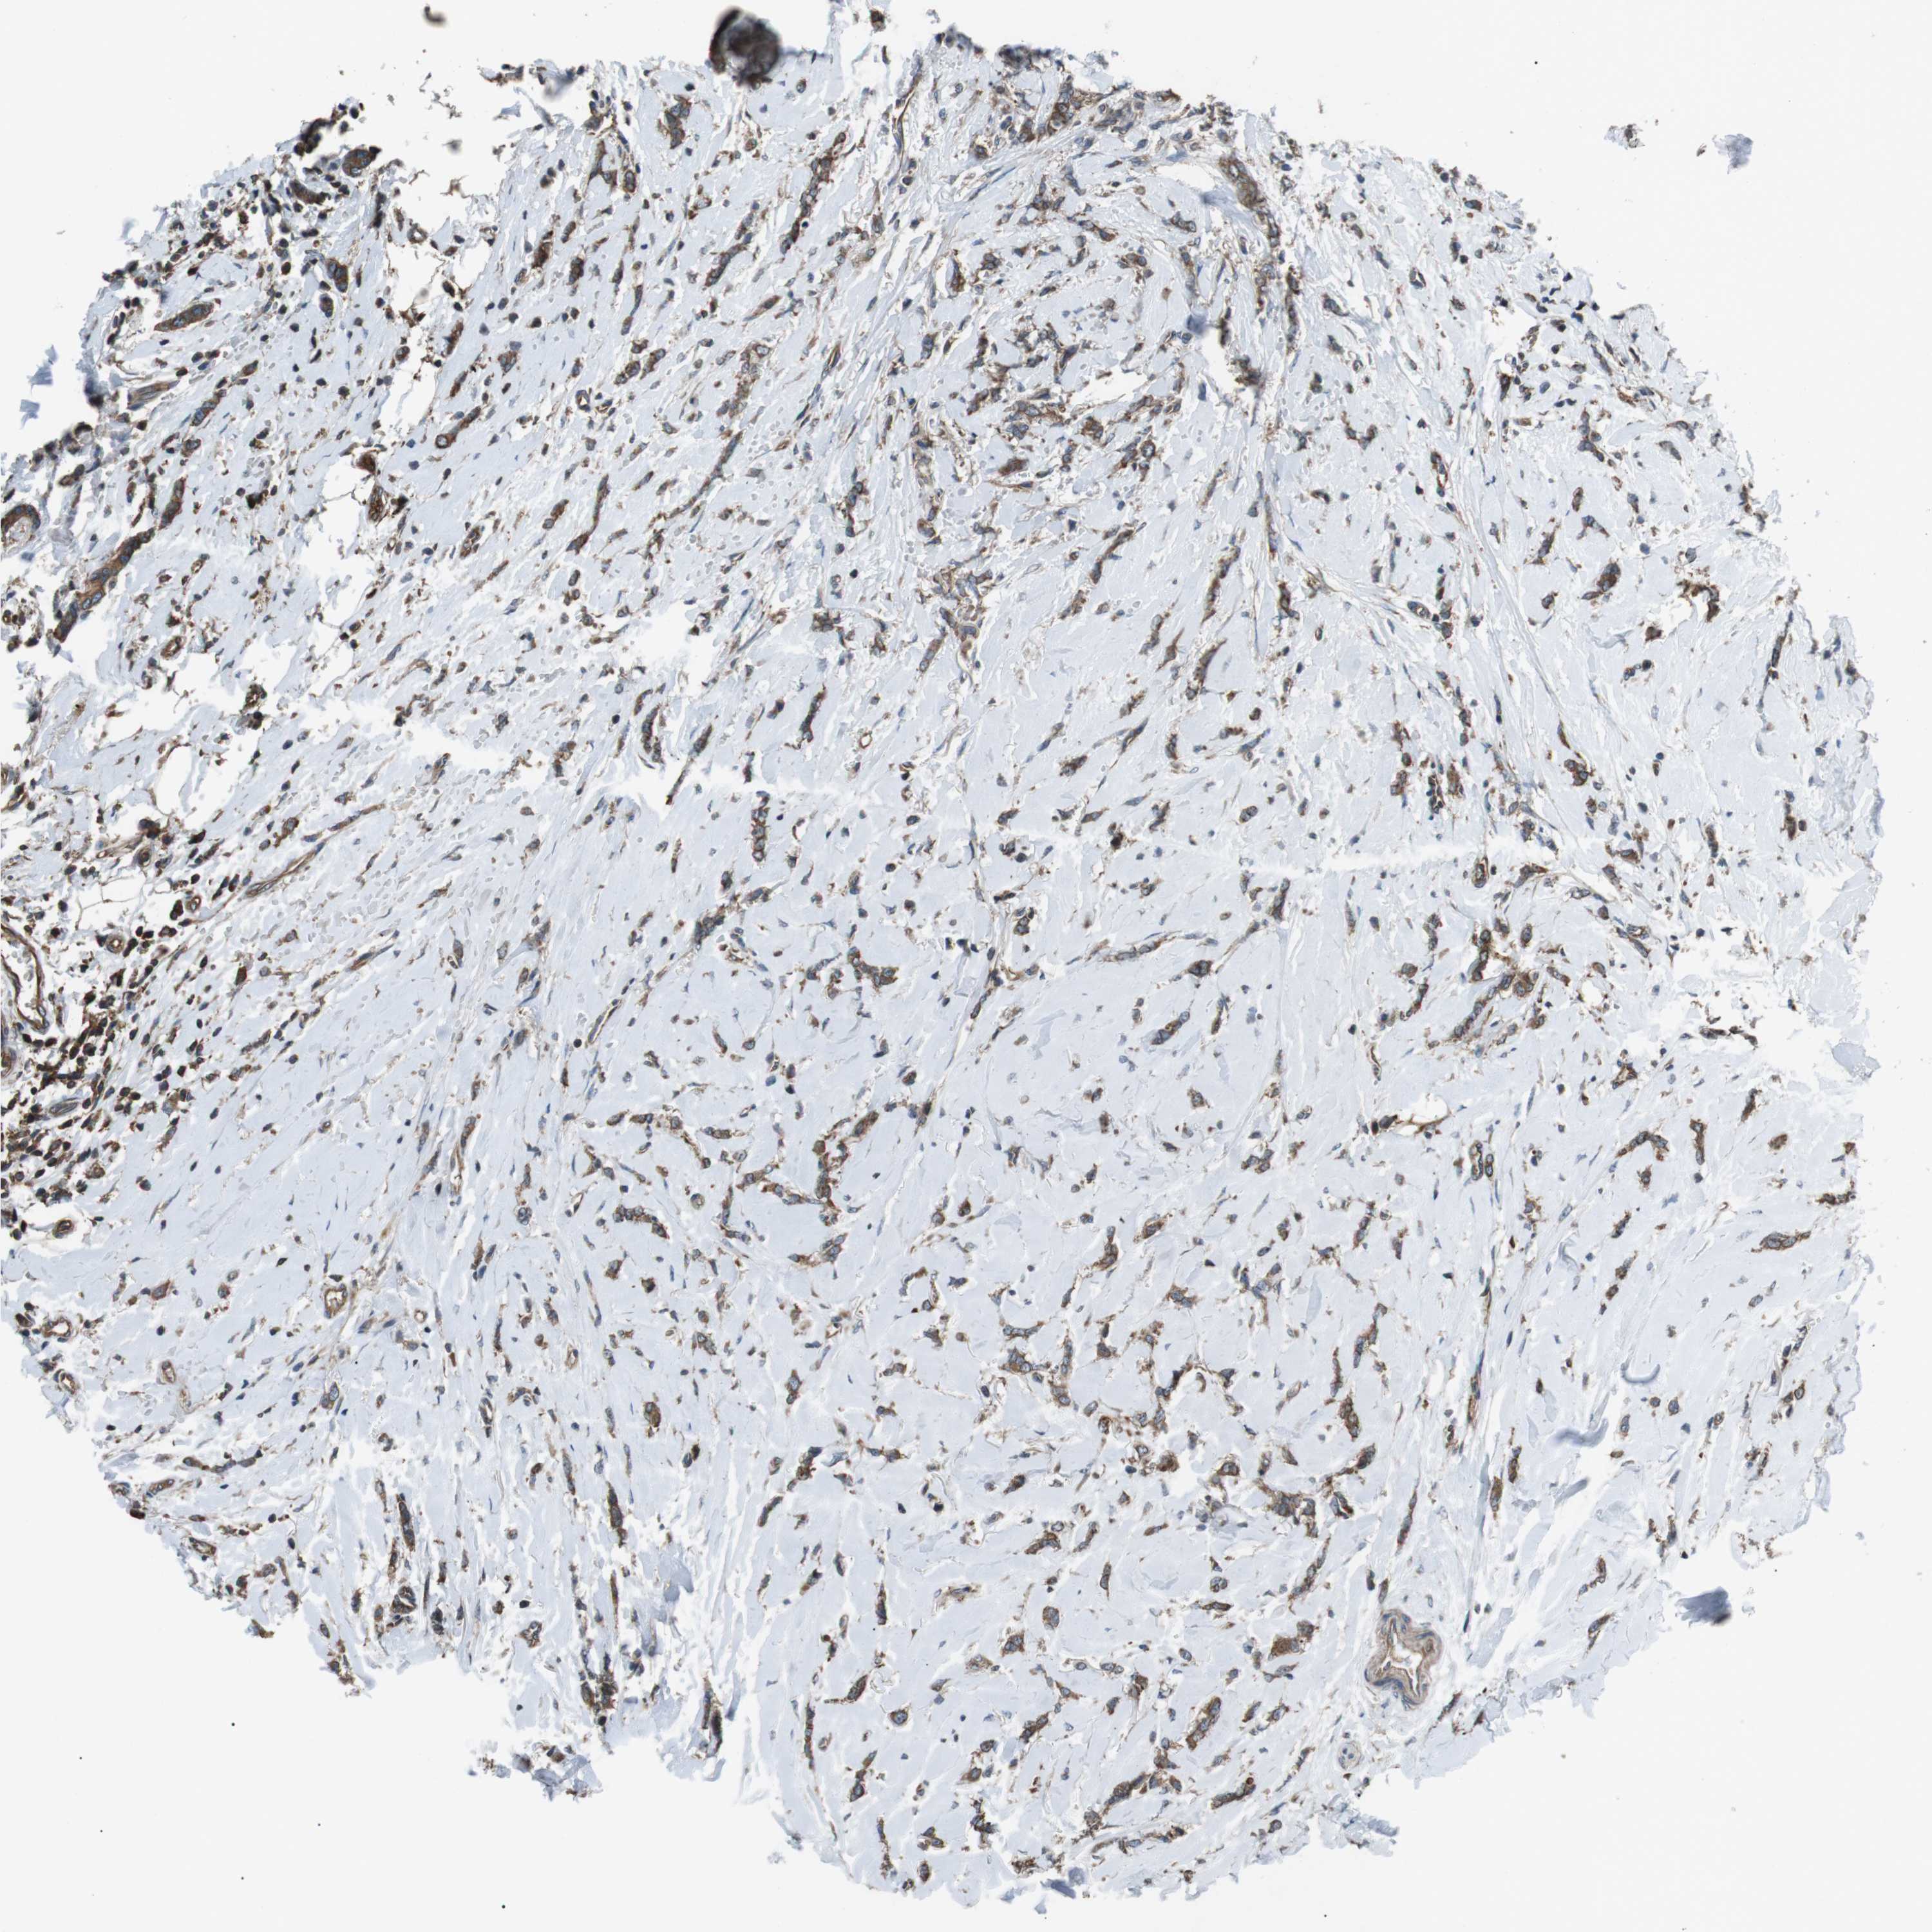

CANCER BREAST CANCER Show tissue menu

BRCA TCGA BRCA VALIDATION PROTEIN EXPRESSION